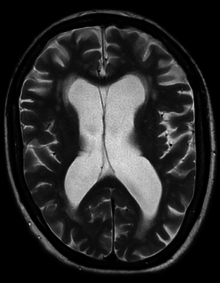

One case of hydrocephalus was a man whose brain shrank to a thin sheet of tissue, due to a buildup of cerebrospinal fluid in his skull. As a child, the man had a shunt, but it was removed when he was 14. In July 2007, at age 44, he went to a hospital due to mild weakness in his left leg. When doctors learned of the man's medical history, they performed a CT and MRI scan, and were astonished to see "massive enlargement" of the lateral ventricles in the skull. Dr. Lionel Feuillet of Hôpital de la Timone in Marseille said, "The images were most unusual... the brain was virtually absent."[39] Intelligence tests showed the person had an IQ of 75, considered "borderline intellectual functioning", just above what would be officially considered mentally challenged.[citation needed]

The person was a married father of two children, and worked as a civil servant, leading an at least superficially normal life, despite having enlarged ventricles with a decreased volume of brain tissue. "What I find amazing to this day is how the brain can deal with something which you think should not be compatible with life", commented Dr. Max Muenke, a pediatric brain-defect specialist at the National Human Genome Research Institute. "If something happens very slowly over quite some time, maybe over decades, the different parts of the brain take up functions that would normally be done by the part that is pushed to the side."[40][41][42]